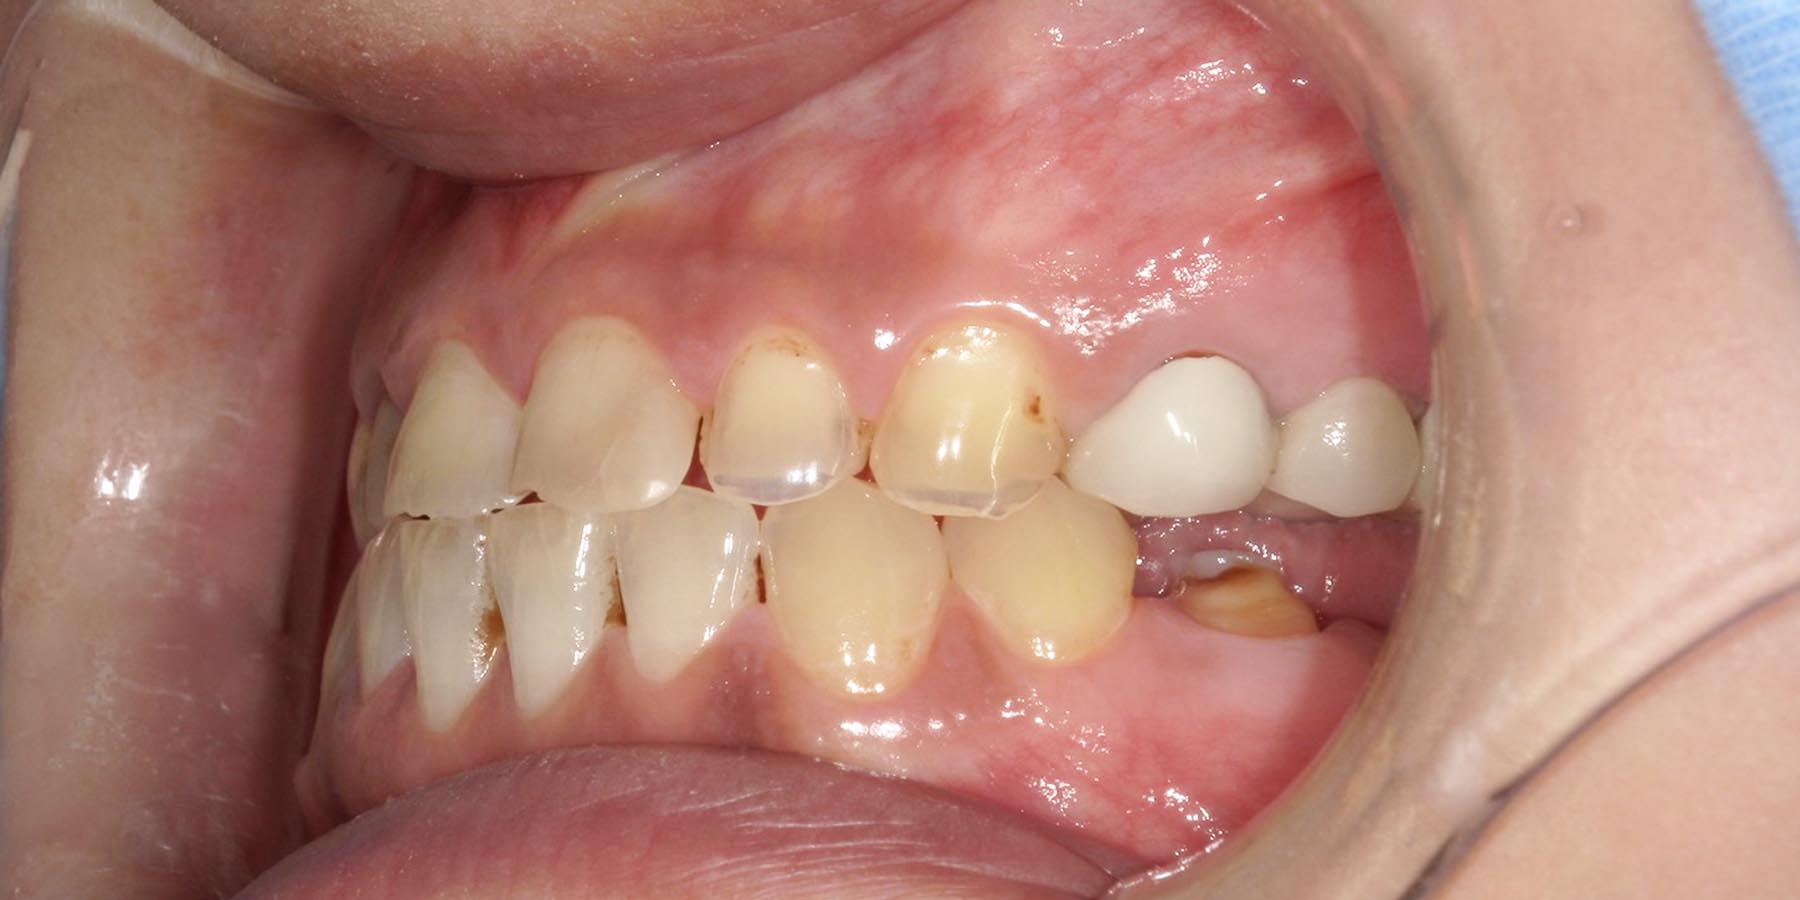

治療前

治療後